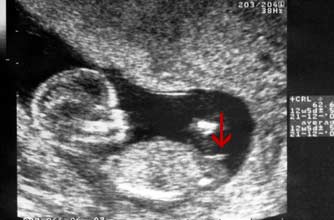

(女宝)

Girl nub: The nub isn't pointing up more than 30 degrees - in fact it's almost horizontal!

小肿块没有指向三十度以上 - 事实上它几乎是水平的!